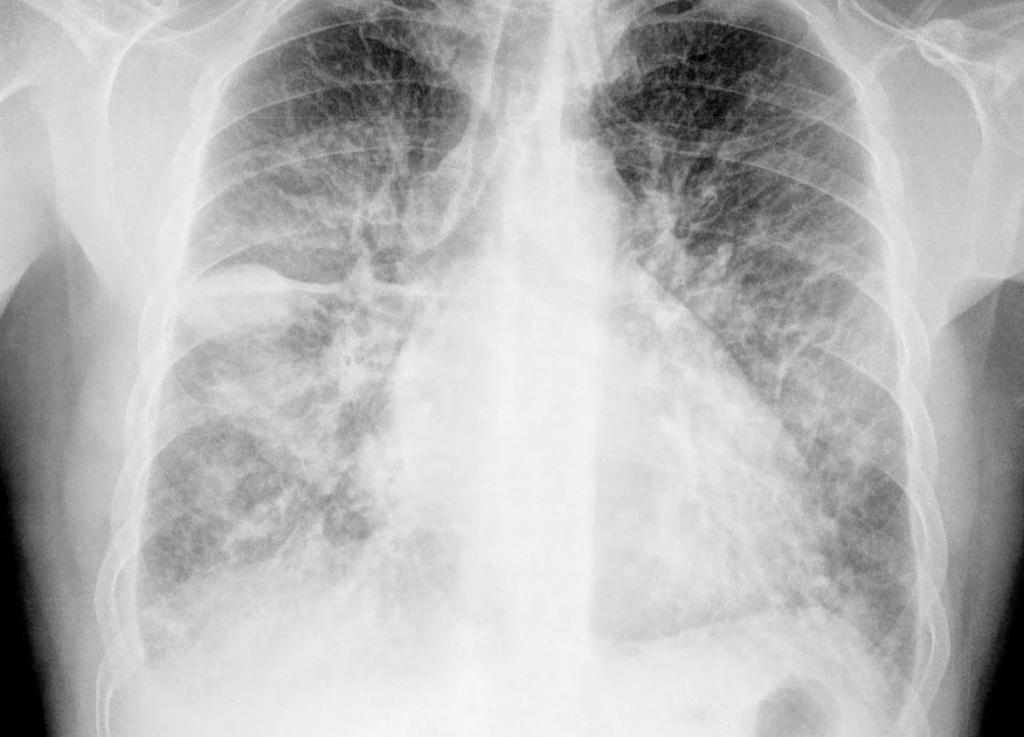

Рентгенография грудной клетки

У 5—10% больных при первом обращении к врачу изменения на рентгенограмме грудной клетки отсутствуют (стадия 0), у 35—45% больных выявляется двустороннее увеличение прикорневых лимфоузлов (стадия I), у 25% — линейные тени, сетчато-узелковое поражение и двустороннее увеличение прикорневых лимфоузлов (стадия II), у 25% — ограниченные затемнения в легких (стадия III). Конечная стадия заболевания (стадия IV) проявляется необратимыми изменениями в легких — пневмосклерозом, смещением корней легких, бронхоэктазами, эмфиземой. Изредка наблюдаются пневмоторакс, односторонний плевральный выпот, единичные или множественные полости и очаговые тени, обызвествление лимфоузлов. КТ и сцинтиграфия легких с галлием при саркоидозе обычно не применяются.